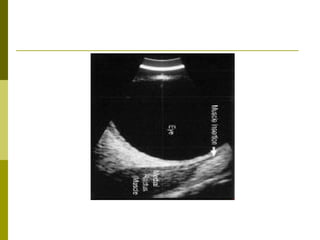

T sign….. arrows

 Scleral thickening,T sign, choroidal effusion